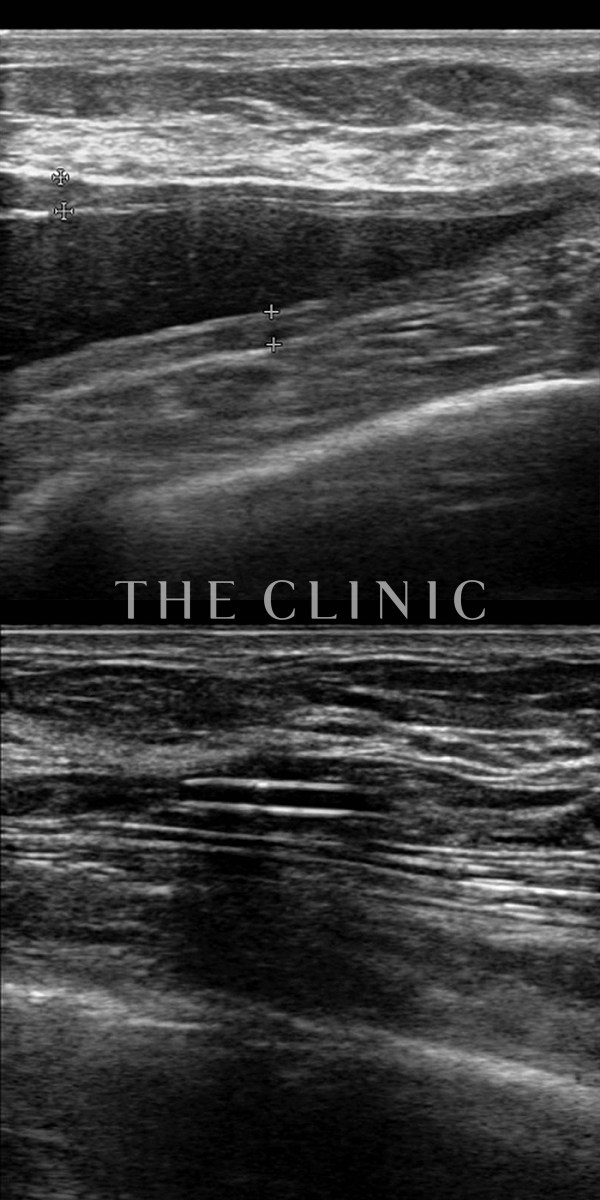

コンデンスリッチ豊胸を行うために、前もってアクアフィリングの除去を行いました。エコーで確認するとかなり厚い被膜が形成されています。

アクアフィリングは生理食塩水で溶解されるとのことで、エコー下に生理食塩水を注入しましたが、なかなか溶解できず、ヒアルロニダーゼも追加してなんとか溶解除去することができました。右側は炎症があった為か、汚く濁った状態でした。